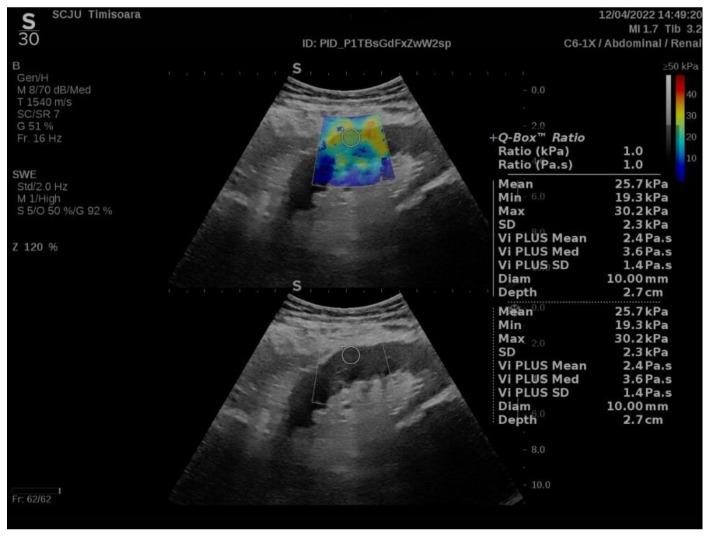

使用二维剪切波弹性成像(2D SWE PLUS)和虚拟触诊组织成像定量分析(Vi PLUS)测量评估肾移植受者的肾移植硬度和黏度——一项初步研究

Assessment of Renal Allograft Stiffness and Viscosity Using 2D SWE PLUS and Vi PLUS Measures-A Pilot Study.

Elastography is a useful noninvasive tool for the assessment of renal transplant recipients. 2D-shear wave elastography (SWE) PLUS and viscosity plane-wave ultrasound (Vi PLUS) have emerged as novel techniques that promise to offer improved renal stiffness and viscosity measures due to improved processing algorithms. Methods: We performed a cross-sectional study of 50 kidney transplanted patients (16 women, 34 men; mean age of 47.5 ± 12.5; mean estimated glomerular filtration rate (eGFR) estimated by Chronic Kidney Disease Epidemiology Collaboration formula: 52.19 ± 22.6 mL/min/1.73 m2; and a mean duration after transplant of 10.09 ± 5 years). For every patient, we obtained five valid measurements of renal stiffness (obtained from five different frames in the cortex of the renal graft), and also tissue viscosity, with a C6-1X convex transducer using the Ultra-Fast™ software available on the Aixplorer Mach 30 ultrasound system (Supersonic Imagine, Aix-en-Provence, France). The median values of elastographic and viscosity measures have been correlated with the patients’ demographic, biological, and clinical parameters. Results: We obtained a cut-off value of renal cortical stiffness of <27.3 kiloPascal(kPa) for detection of eGFR < 60 mL/min/1.73 m2 with 80% sensitivity and 85% specificity (AUC = 0.811, p < 0.0001), a cut-off value of <26.9 kPa for detection of eGFR < 45 mL/min/1.73 m2 with 82.6% sensitivity and 74% specificity (AUC = 0.789, p < 0.0001), and a cut-off value of <23 kPa for detection of eGFR < 30 mL/min/1.73 m2 with 88.8% sensitivity and 75.6% specificity (AUC = 0.852, p < 0.0001). We found a positive correlation coefficient between eGFR and the median measure of renal cortical stiffness (r = 0.5699, p < 0.0001), between eGFR the median measure of viscosity (r = 0.3335, p = 0.0180), between median depth of measures and renal cortical stiffness (r = −0.2795, p = 0.0493), and between median depth of measures and body mass index (BMI) (r = 0.6574, p < 0.0001). Our study showed good intra-operator agreement for both 2D SWE PLUS measures—with an intraclass correlation coefficient (ICC) of 0.9548 and a 95% CI of 0.9315 to 0.9719—and Vi PLUS, with an ICC of 0.8323 and a 95% CI of 0.7457 to 0.8959. The multivariate regression model showed that 2D SWE PLUS values were associated with eGFR, Vi PLUS, and depth of measures. Conclusions: Assessment of renal allograft stiffness and viscosity may prove to be an effective method for identifying patients with chronic allograft injury and could prove to be a low-cost approach to provide additional diagnostic information of kidney transplanted patients.

弹性成像技术是评估肾移植受者的一种有用的非侵入性工具。二维剪切波弹性成像(SWE)PLUS和粘性平面波超声(Vi PLUS)已成为新技术,由于处理算法的改进,有望提供更好的肾脏硬度和粘度测量值。方法:我们对50例肾移植患者进行了一项横断面研究(16名女性,34名男性;平均年龄47.5±12.5岁;根据慢性肾脏病流行病学协作公式估算的平均肾小球滤过率(eGFR):52.19±22.6 mL/min/1.73 m²;移植后平均时间为10.09±5年)。对于每位患者,我们使用Aixplorer Mach 30超声系统(法国普罗旺斯艾克斯的Supersonic Imagine公司)上的Ultra-Fast™软件,通过C6-1X凸阵探头获得了五次有效的肾脏硬度测量值(从肾移植皮质的五个不同帧中获取)以及组织粘度。弹性成像和粘度测量的中位数已与患者的人口统计学、生物学和临床参数相关联。结果:我们获得了肾皮质硬度的临界值<27.3千帕斯卡(kPa),用于检测eGFR<60 mL/min/1.73 m²,灵敏度为80%,特异性为85%(AUC = 0.811,p<0.0001);临界值<26.9 kPa用于检测eGFR<45 mL/min/1.73 m²,灵敏度为82.6%,特异性为74%(AUC = 0.789,p<0.0001);临界值<23 kPa用于检测eGFR<30 mL/min/1.73 m²,灵敏度为88.8%,特异性为75.6%(AUC = 0.852,p<0.0001)。我们发现eGFR与肾皮质硬度的中位数测量值之间存在正相关系数(r = 0.5699,p<0.0001),eGFR与粘度的中位数测量值之间存在正相关系数(r = 0.3335,p = 0.0180),测量的中位数深度与肾皮质硬度之间存在负相关系数(r = -0.2795,p = 0.0493),测量的中位数深度与体重指数(BMI)之间存在正相关系数(r = 0.6574,p<0.0001)。我们的研究表明,对于二维SWE PLUS测量,操作者内一致性良好——组内相关系数(ICC)为0.9548,95%置信区间为0.9315至0.9719——对于Vi PLUS,ICC为0.8323,95%置信区间为0.7457至0.8959。多元回归模型表明,二维SWE PLUS值与eGFR、Vi PLUS和测量深度相关。结论:评估同种异体肾移植的硬度和粘度可能被证明是识别慢性同种异体移植损伤患者的有效方法,并且可能被证明是一种低成本的方法,可为肾移植患者提供额外的诊断信息。